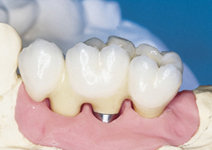

Protetické řešení může být pomocí můstku, který je kotvený na implantátech nebo pomocí jednotlivých korunek na implantátech.

V zásadě je možné do těchto můstků zařadit i přirozené zuby, zejména pokud je potřeba tyto zuby ošetřit proteticky – korunkami. Korunky nebo můstky mohou být na implantáty nacementovány nebo přišroubovány.

Zdravé zuby zůstanou zachovány a přitom náhrady jsou pevné, jako na vlastních zubech